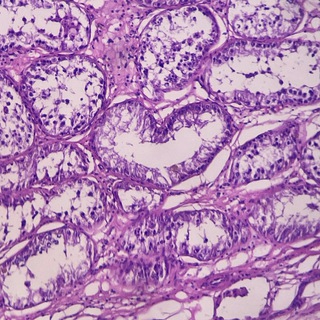

Группа ветеринарного патолога, который рассказывает о необычных и обычных случаях из своей лабораторной практики.

#ветеринария #гистология #патология